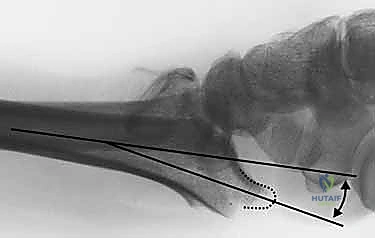

- الأشعة السينية (X-rays):

هي الخطوة الأولى لتقييم الكسر. يتم أخذ صور من زوايا متعددة (أمامية خلفية، جانبية، ومائلة) لتحديد موقع الكسر الأساسي ودرجة الانزياح والتقصير في عظم الكعبرة.

- التصوير المقطعي المحوسب (CT Scan) مع إعادة البناء ثلاثي الأبعاد:

هذا هو المعيار الذهبي الذي يعتمده الدكتور هطيف لجميع كسور المفصل المعقدة. تتيح الأشعة المقطعية رؤية كل شظية عظمية بوضوح تام، وتحديد حجمها، وموقعها، ودرجة تفتت السطح المفصلي بدقة ملليمترية. من خلال إعادة البناء ثلاثي الأبعاد (3D Reconstruction)، يمكن للدكتور هطيف "رؤية" الكسر من جميع الزوايا قبل فتح الجلد، مما يسمح له باختيار الغرسات (الصفائح والمسامير) الدقيقة لكل شظية وتحديد المداخل الجراحية المثلى.